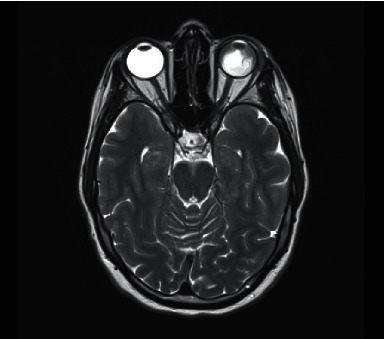

我们为大家介绍一例罕见病例:一名 39 岁女性在接受异体造血干细胞移植 2 个月后,左眼孤立性急性髓性白血病(AML)髓外复发。她最初出现无痛性左眼红斑、肿胀和视力障碍。眼科初步检查发现结膜化生、眼压升高和浆液性视网膜脱离。她最初因疑似眼眶蜂窝组织炎接受了静脉注射抗生素和抗真菌治疗,但临床症状有所进展,因此又接受了静脉注射皮质类固醇治疗。一周后,她的病情发展为闭角型青光眼,出现了眼睑下垂和结膜下肿块增大。她接受了紧急结膜下活检和视网膜下积液引流,结果证实急性髓外性白血病复发。值得注意的是,进一步检查没有发现骨髓或中枢神经系统复发的证据。她接受了局部放疗,结膜下肿块和浆液性视网膜脱离逐渐消退,并考虑接受供体淋巴细胞输注和阿扎胞苷治疗;不幸的是,她出现了呼吸道败血症,虽经全力抢救仍不幸去世。本病例是急性髓细胞性白血病孤立性眼部髓外复发的罕见病例,强调了临床高度怀疑该病时早期眼科介入和组织活检的重要性。

We present a rare case of a 39-year-old female with extramedullary relapse of acute myeloid leukaemia (AML) isolated to the left eye 2 months post allogeneic haematopoietic stem cell transplant. She initially presented with painless left eye erythema, swelling, and visual impairment. Initial ophthalmology review revealed conjunctival chemosis, raised intraocular pressure, and serous retinal detachments. She was initially treated for suspected orbital cellulitis with intravenous antibiotic and antifungal therapy but clinically progressed so was then treated with intravenous corticosteroids. One week later, she progressed to angle-closure glaucoma with development of a hypopyon and an enlarging subconjunctival mass. She proceeded to urgent subconjunctival biopsy and drainage of subretinal fluid which confirmed extramedullary relapse of AML. Notably, further investigation found no evidence of bone marrow or central nervous system relapse. She proceeded to localized radiotherapy with gradual resolution of the subconjunctival mass and serous retinal detachment and was for consideration of donor lymphocyte infusions and azacitidine therapy; unfortunately, she developed respiratory sepsis and passed away despite maximal efforts. This case represents a rare and unusual presentation of isolated ocular extramedullary relapse of AML and emphasises the importance of early ophthalmology involvement and tissue biopsy when there is high clinical suspicion of the disease.